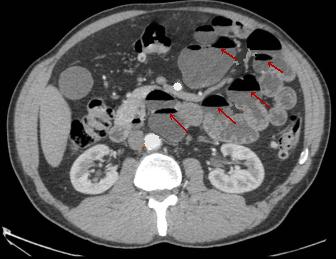

| Image TDM en coupe axiale du

diverticule multiple du grele . Image hydroaerique

des diverticule le long de l'intestin (fleche rouge

) . La paroi du diverticule est tres mince , en

differentiel avec la paroi de l'intestin ou du

colon, sa paroi est plus epaissisement que la

diverticule . |

|

Diverticule de

l'intestin : Aspect radiologique TDM en coupe axiale

. Image hydroaerique avec sa paroi tres mince .. |